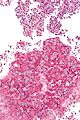

Pneumocystis pneumonia

• Abbreviated PCP.

• AKA Pneumocystis jirovecii pneumonia.

General

• Organism: pneumocystis,

• Specific organism: Pneumocystis jirovecii[16] (used to be called Pneumocystis carinii).

• May be spelled Pneumocystis jiroveci.

• Fungus... used to be considered a parasite.

• Typical location: lung.

Clinical:

• Opportunistic infection - typically in HIV +ve individuals.

• May have subtle findings on chest X-ray.

Microscopic

Features:

• Form frothy aggregates that take the shape of the alveoli they sit within, i.e. they form "alveolar casts".

• "Dented ping-pong ball" appearance.[9] **Remember PCP = ping-pong.

• Approximately 7-8 μm in size.